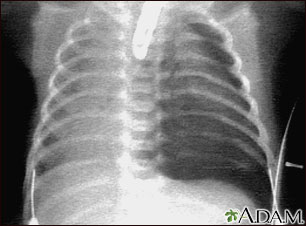

X-Rays. A chest x-ray is nearly always taken on a patient admitted to the hospital to confirm a pneumonia diagnosis. This does not need to be repeated if the patient gets better.

A chest x-ray may reveal the following: